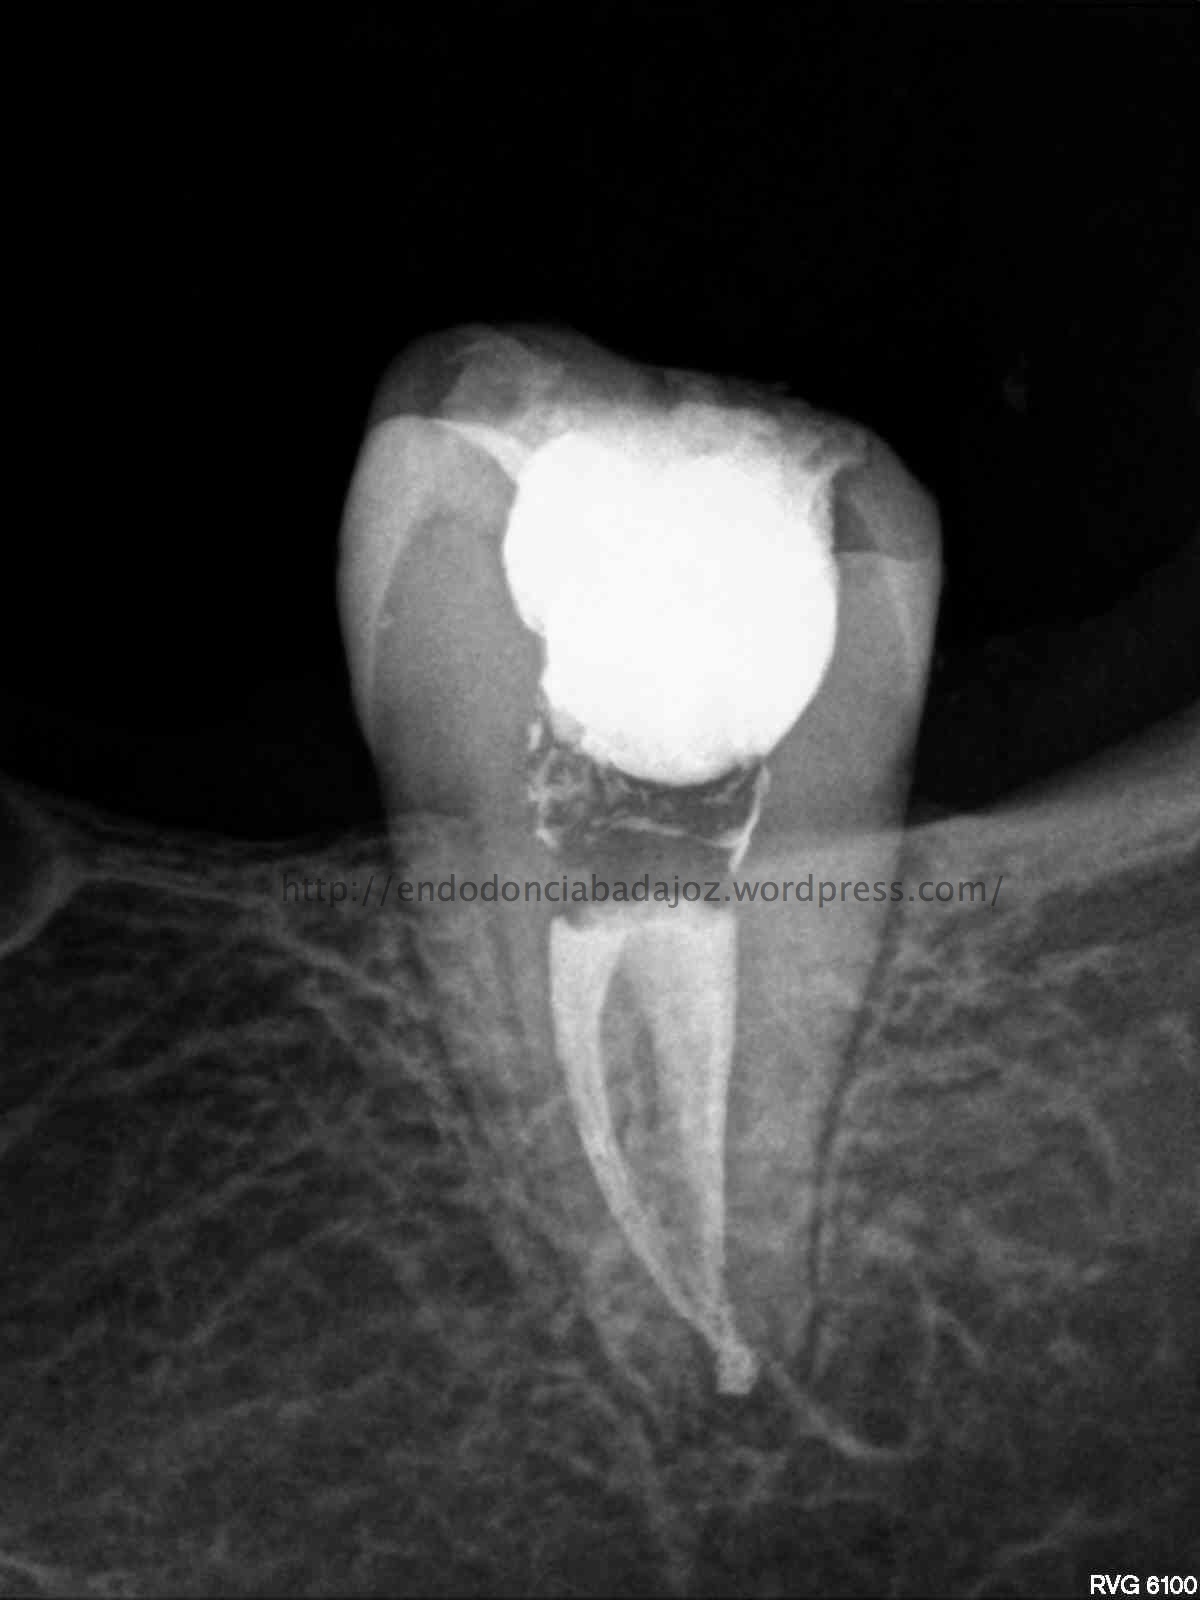

Se trata de un par de molares inferiores con lesiones apicales (Periodontitis apicales crónicas ). Consecuencia de caries profundas en su momento.

Se tratan del caso A y el caso B, por orden de posición, ambos casos se instrumentaron de la misma manera, elegimos Protaper hasta una F2, ambos casos se realizaron en una sesión tras abundante irrigación y finalmente se obturaron con condensación Vertical con la técnica de Ola continua de Buchanan complementando en el backfilling con guatpercha inyectada con la Pistola Obtura II.

Caso A:

Llamamos a la paciente a revisión a los 10 meses:

Caso B:

También se llamo a revisión a los 10 meses.